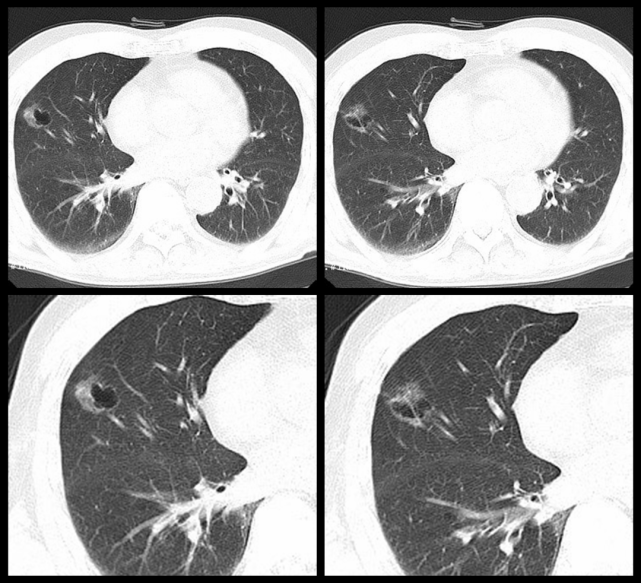

肺肿瘤ct图片表现